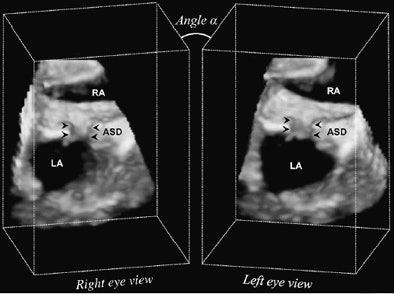

| The volumetric dataset of the created ASD (arrowheads) is sampled using parallel projection. Rays are cast simultaneously in a front-to-back fashion through the 3D ultrasound data. Left-eye and right-eye views are separately generated by rendering the 3D ultrasound volume from two viewpoints skewed by angle A. LA = left atrium; RA = right atrium. Image published with permission of the Journal of Thoracic and Cardiovascular Surgery. |